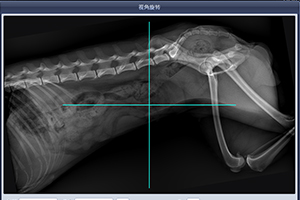

有。我们可以用另外一个途径来面对这个问题—Q角。

Q角(quadriceps-angle)  [ˈkwɔ:driseps] 书面语叫股四头肌夹角。它指髂前上棘至髌骨中心点连线与髌骨中心至胫骨结节中心连线所形成的夹角。正常Q角动物约为10°~15°(人的应该在5°~10°)。若Q角大于15°则股四头肌收缩时产生使髌骨向外移动的分力。随着Q角的增大向外侧牵拉髌骨的分力逐渐增大,髌骨稳定性也越来越差。加之在剧烈运动过程中的不确定力,髌骨可游离出滑车沟。所以髌骨脱位很容易发生。

犬髌股关节的稳定性受到滑车沟的几何形态影响,包括其深度和坡度。滑车沟的几何形态及外形比较复杂,其长轴的截面是不等的。滑车沟外侧面最高点位于股骨外髁的前面,并向远端及后方逐渐下降,在伸膝和屈膝早期,这种结构很好地限制了髌骨的移动。在伸膝状态下,股四头肌腱和髌韧带的张力最低。抵消了滑车骨性结构的限制,对提高伸膝和轻度屈膝时的髌骨稳定性具有重要作用。

Q角的判读方法: